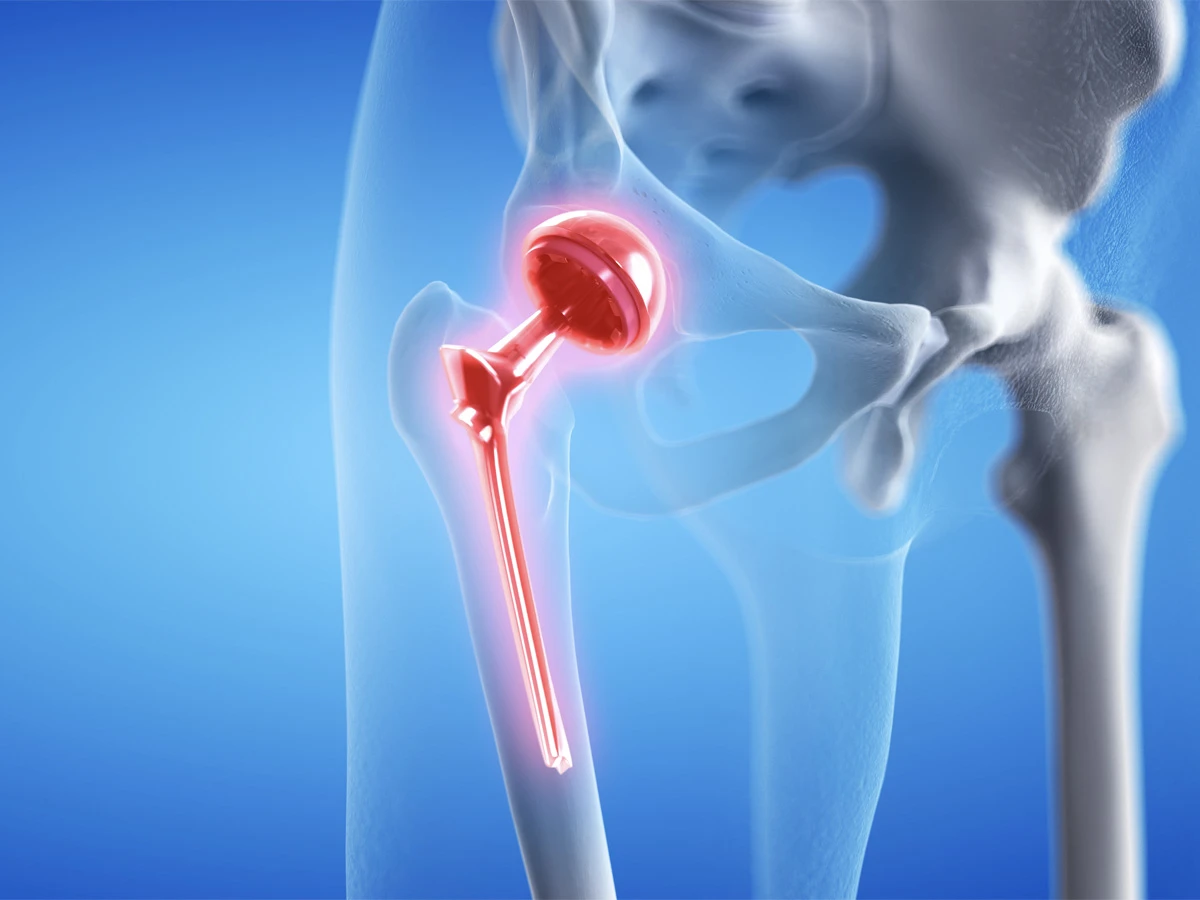

La chirurgia della protesi dell’anca ha compiuto enormi progressi negli ultimi anni, offrendo soluzioni sempre più efficaci e meno invasive per migliorare la qualità della vita dei pazienti. Tra le tecniche più innovative, l’accesso mini-invasivo per via anteriore rappresenta un’importante evoluzione rispetto ai metodi tradizionali, garantendo un recupero più rapido e minori disagi post-operatori.

L’accesso mini-invasivo per via anteriore è una tecnica chirurgica avanzata che consente di impiantare una protesi dell’anca attraverso un’incisione ridotta nella parte anteriore della coscia. A differenza delle tecniche tradizionali, questo approccio permette di preservare muscoli e tendini circostanti, riducendo il trauma chirurgico e favorendo una ripresa più veloce.

L’approccio mini-invasivo per via anteriore rappresenta una delle opzioni più avanzate per la sostituzione protesica dell’anca. Grazie ai suoi numerosi vantaggi, questa tecnica consente di ottenere un recupero più rapido e meno traumatico rispetto alle metodiche tradizionali. Tuttavia, la scelta della tecnica chirurgica più adatta deve essere sempre valutata con un ortopedico specializzato, che analizzerà il caso specifico per garantire il miglior risultato possibile.